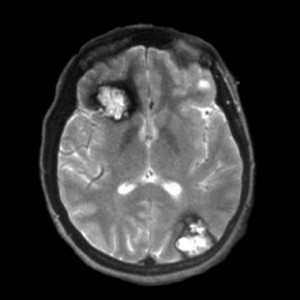

![кавернома мрт]()

Аксиальные МРТ-изображения в режиме градиентного эхо позволяют достичь лучшей визуализации крупных кавернозных ангиом в правой лобной и левой затылочной долях. Гемосидериновый ободок представлен в виде ореола вследствие повышенной магнитной восприимчивости гемосидерина.

Более мелкие каверномы выглядят на Т1- и Т2-взвешенных изображениях как узелковые очаги низкой интенсивности.

Образования небольшого размера лучше визуализируются на изображениях в режиме градиентного эхо благодаря повышенной чувствительности к изменениям магнитного поля, которая свойственна таким импульсным последовательностям. Также было показано, что на последовательных снимках в режиме градиентного эхо мелкие точечные образования лучше визуализируются при удлинении времени эхо; эти данные позволяют предположить, что такие образования содержат парамагнетические вещества.